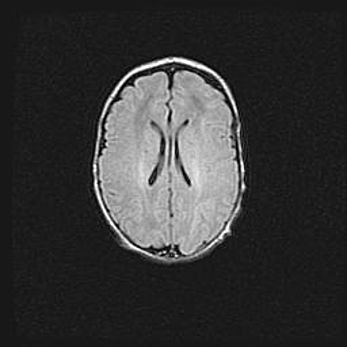

Лейкомаляция с кистозно-глиозной дегенерацией головного мозга.

Возраст: 2 месяца 25 дней

Вес: 6400 г

Окружность головы: 40 см

Срок гестации: 41 неделя

Лейкомаляцию относят к ишемически-гипоксическим повреждениям головного мозга, диагностируемым у новорожденных. При лейкомаляции в головном мозге обнаруживают очаги некроза, возникшие после тяжелой гипоксии и нарушения кровотока. В процессе морфогенеза очаги проходят три стадии: 1) развития некроза, 2) резорбции и 3) формирования глиозного рубца или кисты. Перивентрикулярная лейкомаляция (ПЛ) встречается примерно в 12% случаев среди новорожденных, обычно – у недоношенных детей, причем, частота ее зависит от массы, с которой младенец появился на свет. Наибольшее число малышей страдает лейкомаляцией, если масса при рождении 1500-2500 г.